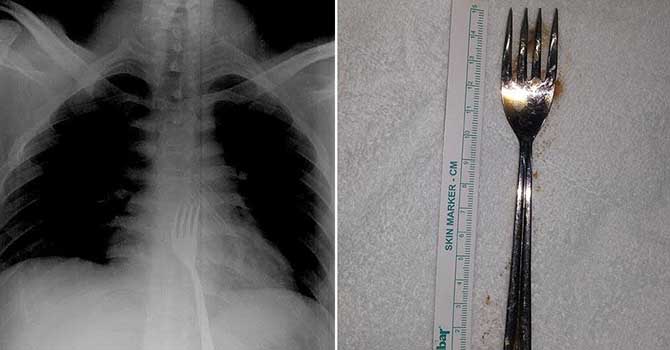

Yuttuğu 15 santimetrelik çatal ameliyatla çıkarıldı